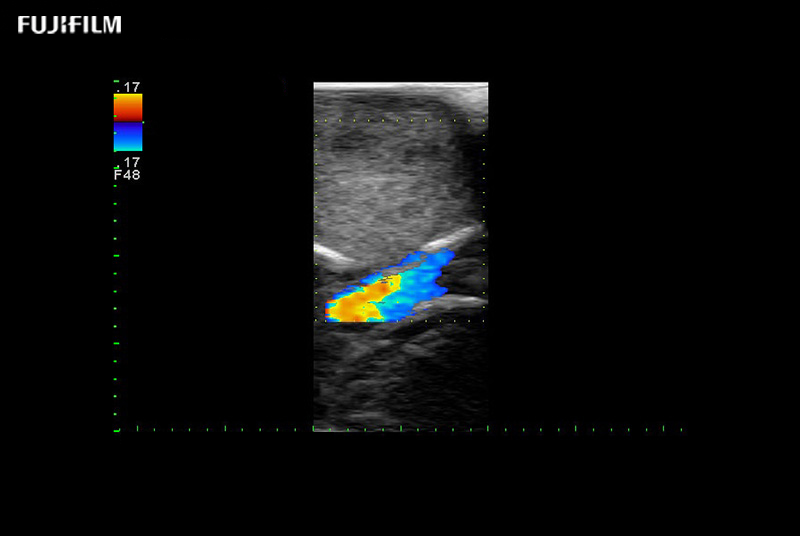

Exclusive 10mm side‐fire linear array transducer with 2.87mm diameter is ideal for real‐time visualization through and behind structures and instant, scalable definition of anatomy and vascularity including the ability to delineate and define tumor margins.

Main Specifications: